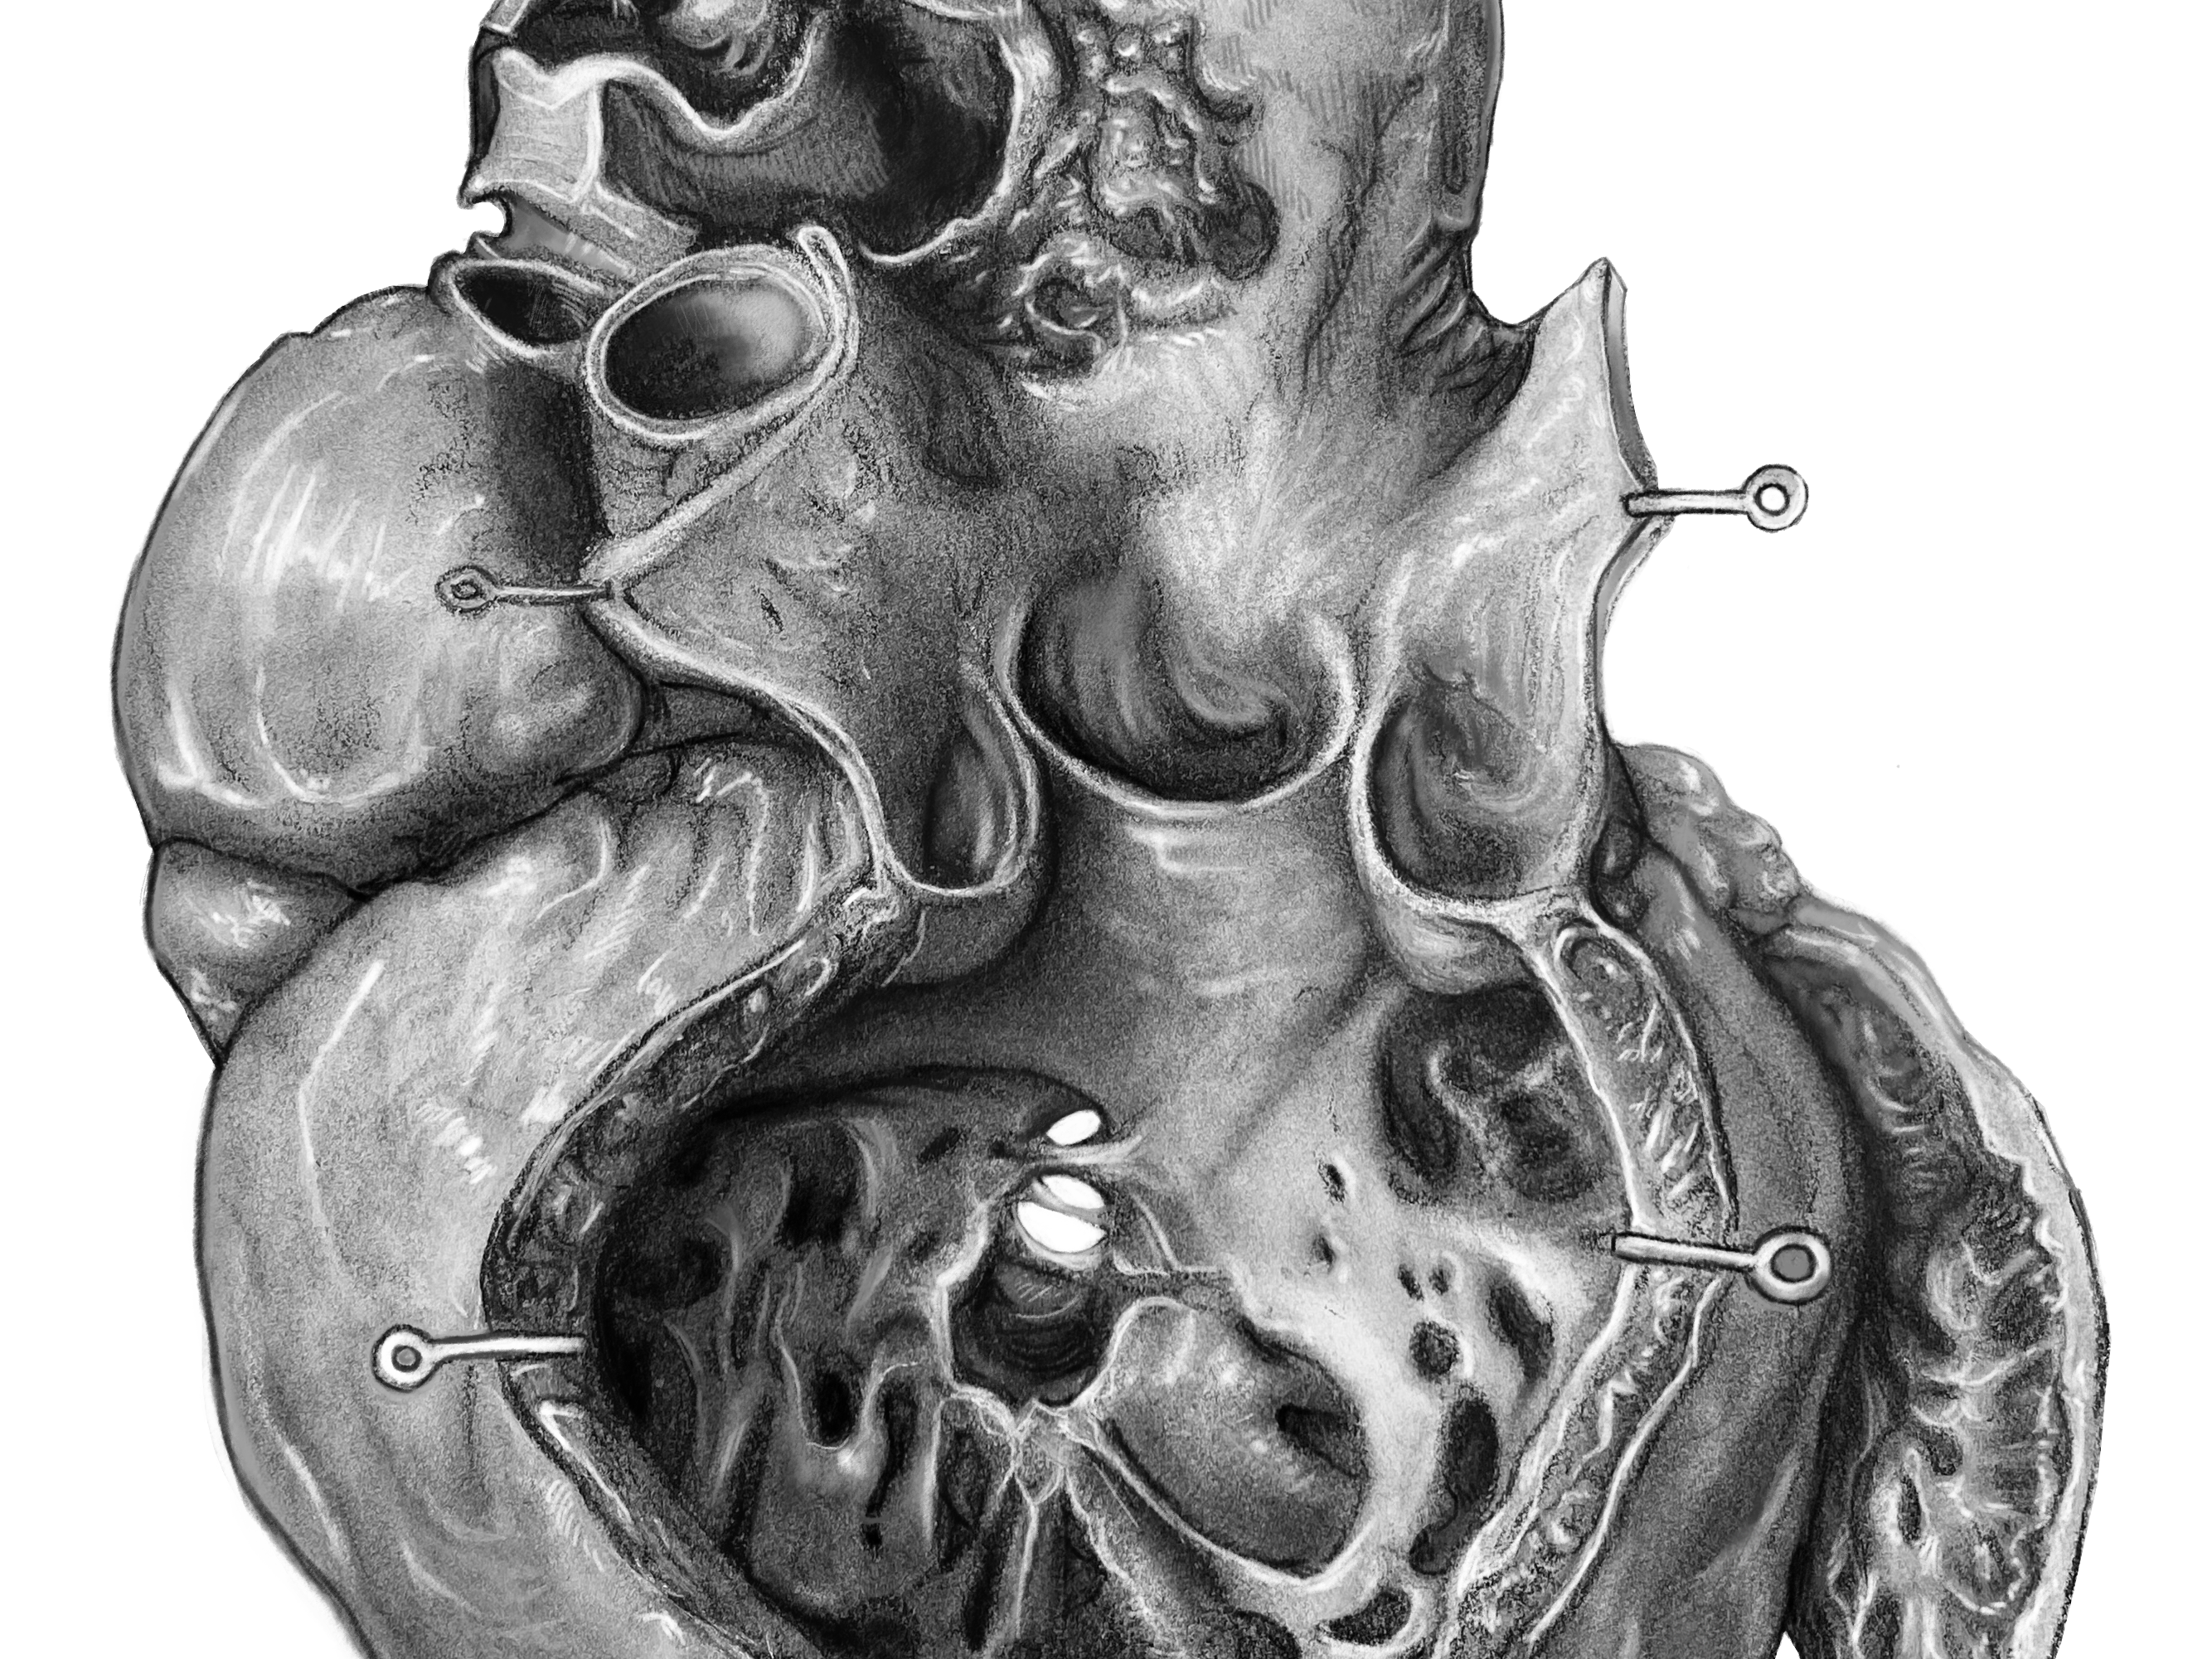

Study of Max Brödel Heart

2024

Anatomical Illustration | Carbon Dust | Client: Shelley Wall